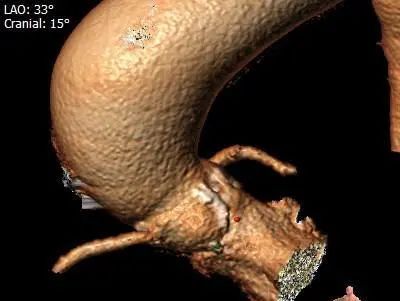

2.Type0型二叶式主动脉瓣狭窄跨瓣困难,故推荐跨瓣、球扩、释放共同采用接近双窦展开角度LAO 33 CRA 15 左右(双窦展开角度过大难以实现)。

术前评估:

冠脉评估及钙化